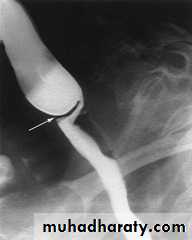

Chest x-ray may be abnormal in late dis., with widening of mediastinum (oesophageal dilatation) and presence of aspiration pneumonitis.Barium swallows . Tapered narrowing (bird beak) of the lower oesophagus and dilating body of oesophagus, a peristaltic and food filled (sigmoid oesophagus).